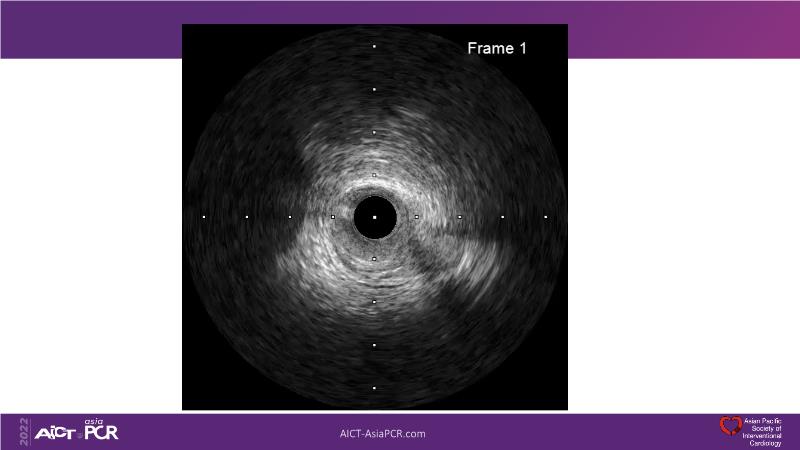

With this session, keep up to date on the evidence, trials and outcome data for intravascular lithotripsy in severely calcified lesions. Learn how to use this technique in real-world patients and understand its role in the treatment algorithm for severely calcified coronary lesions.

- To know the evidence, trials and outcome data for intravascular lithotripsy in severely calcified lesions